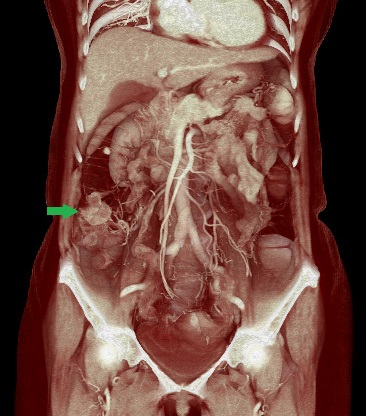

320列CTが導入されています。最短0.275秒/回転であり、心臓CTやCTアンギオに威力を発揮します。新しい機械で、通常のCT検査でも高画質を得ながら被ばく線量を抑えることも可能です。

CTコロノグラフィー:上行結腸癌術前検査

当院は大腸CT検査技術施設認定を取得しています